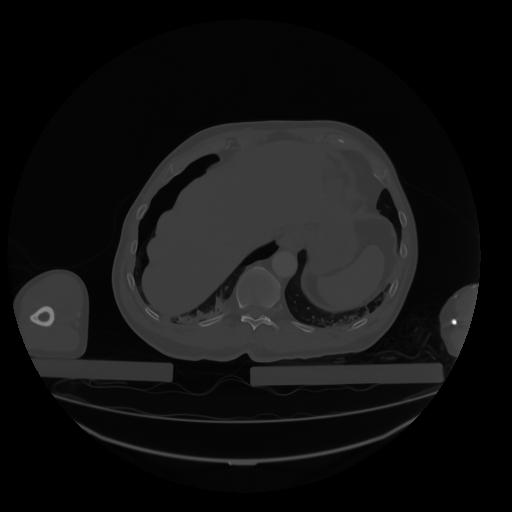

28 CUERPO,CE,Vol,2.0,CUERPO,,